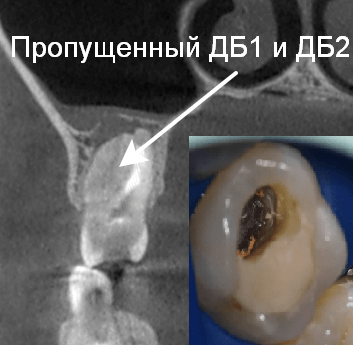

Так в следующем клиническом случае лечения апикального периодонтита мы наблюдаем очаг «воспаления» на верхушке проблемного зуба (рис. 10). Причина воспаления : инфекция в необработанных и незапломбированных каналах (рис. 11). После проведенной процедуры перелечивания системы корневых каналов (их оказалось 6, вместо ожидаемых 4!) под микроскопом мы убрали источник и воспаления и запустили иммунитет на восстановление костной ткани! На контрольных рентгенограммах мы наблюдаем полное восстановление от воспалительного процесса (рис 12).

Рис. 10. Воспалительный очаг на верхушке зуба

Рис. 11. Пропущенные корневые каналы